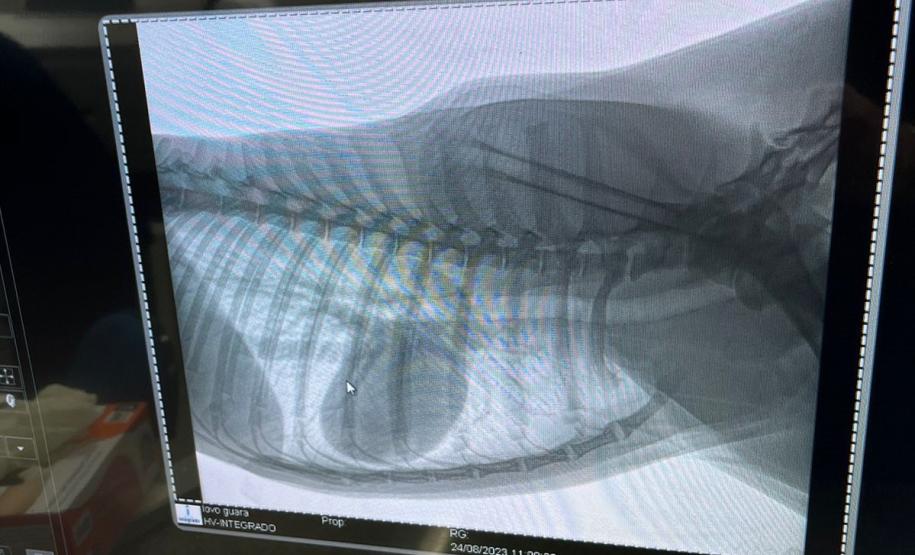

Acionado, o IAT encaminhou o animal, um macho adulto de 30 quilos e com aproximadamente 3 anos, para uma bateria de exames na clínica veterinária que funciona no campus do Centro Universitário Integrado, em Campo Mourão. A confirmação do bom estado de saúde permitiu a soltura do lobo-guará em uma das florestas da região. A ação contou com o apoio do Batalhão de Polícia Ambiental - Força Verde.